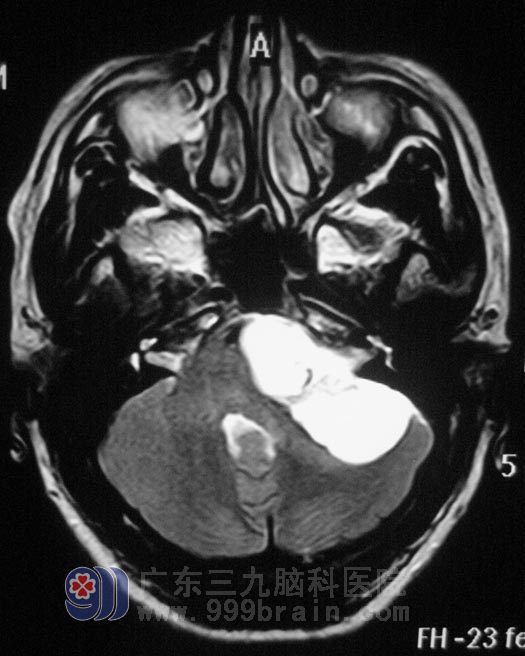

谢先生在一年前开始出现左耳听力变差,未行检查治疗,左侧听力进行性下降,伴间断性伴头痛,可忍受。头颅MRI结果提示:左侧桥小脑角区囊实性占位,考虑神经鞘瘤可能。

10月27日,广东三九脑科医院综合神经外科 鲁明主任主刀,在全麻下行左侧桥小脑角占位切除术+颅内压探头植入术,在显微镜下探查见桥小脑角鱼肉状肿瘤,包膜完整、血运丰富、质软、边界尚清,见肿瘤向前深入内听道,术中对三叉神经、后组颅神经等保护完好,手术顺利结束。术后病理结果为:(左侧桥小脑角区)神经鞘膜瘤。